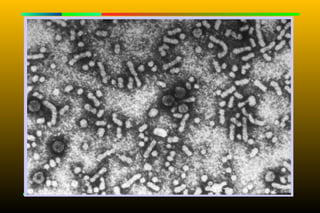

Decoy Particles



HBsAg-containing particles

are released into the serum of

infected people and

outnumber the actual virions.

Spherical or filamentous

They are immunogenic and

were processed into the first

commercial vaccine against

HBV.

Structure      HBcAg HBsAg HBeAg

15-25nm

42nm

HBsAg           20×20×200nm

28nm

HBcAg

DNA

HBeAg

Decoy Particles  HBsAg-containing particles are released into the serum of infected people and outnumber the actual virions.  Spherical or filamentous  They are immunogenic and were processed into the first commercial vaccine against HBV.

• 34.

15-25nm 42nm HBsAg 20×20×200nm 28nm HBcAg DNA HBeAg